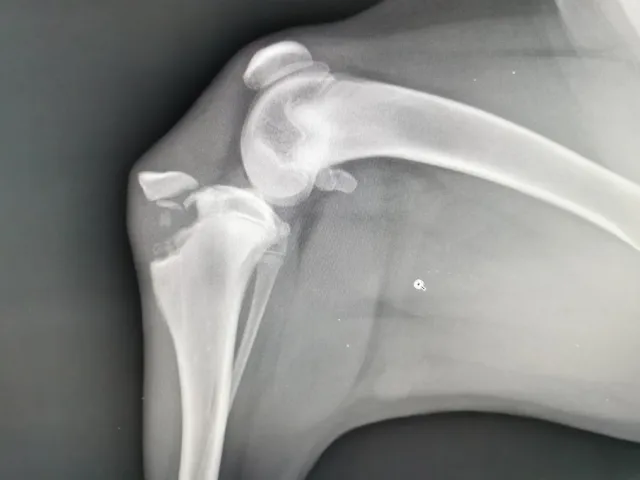

Diagnostica avanzata

Ecografie, radiologie digitali ed esami di laboratorio

Ortopedia e traumatologia

Cura delle lesioni e delle problematiche articolari